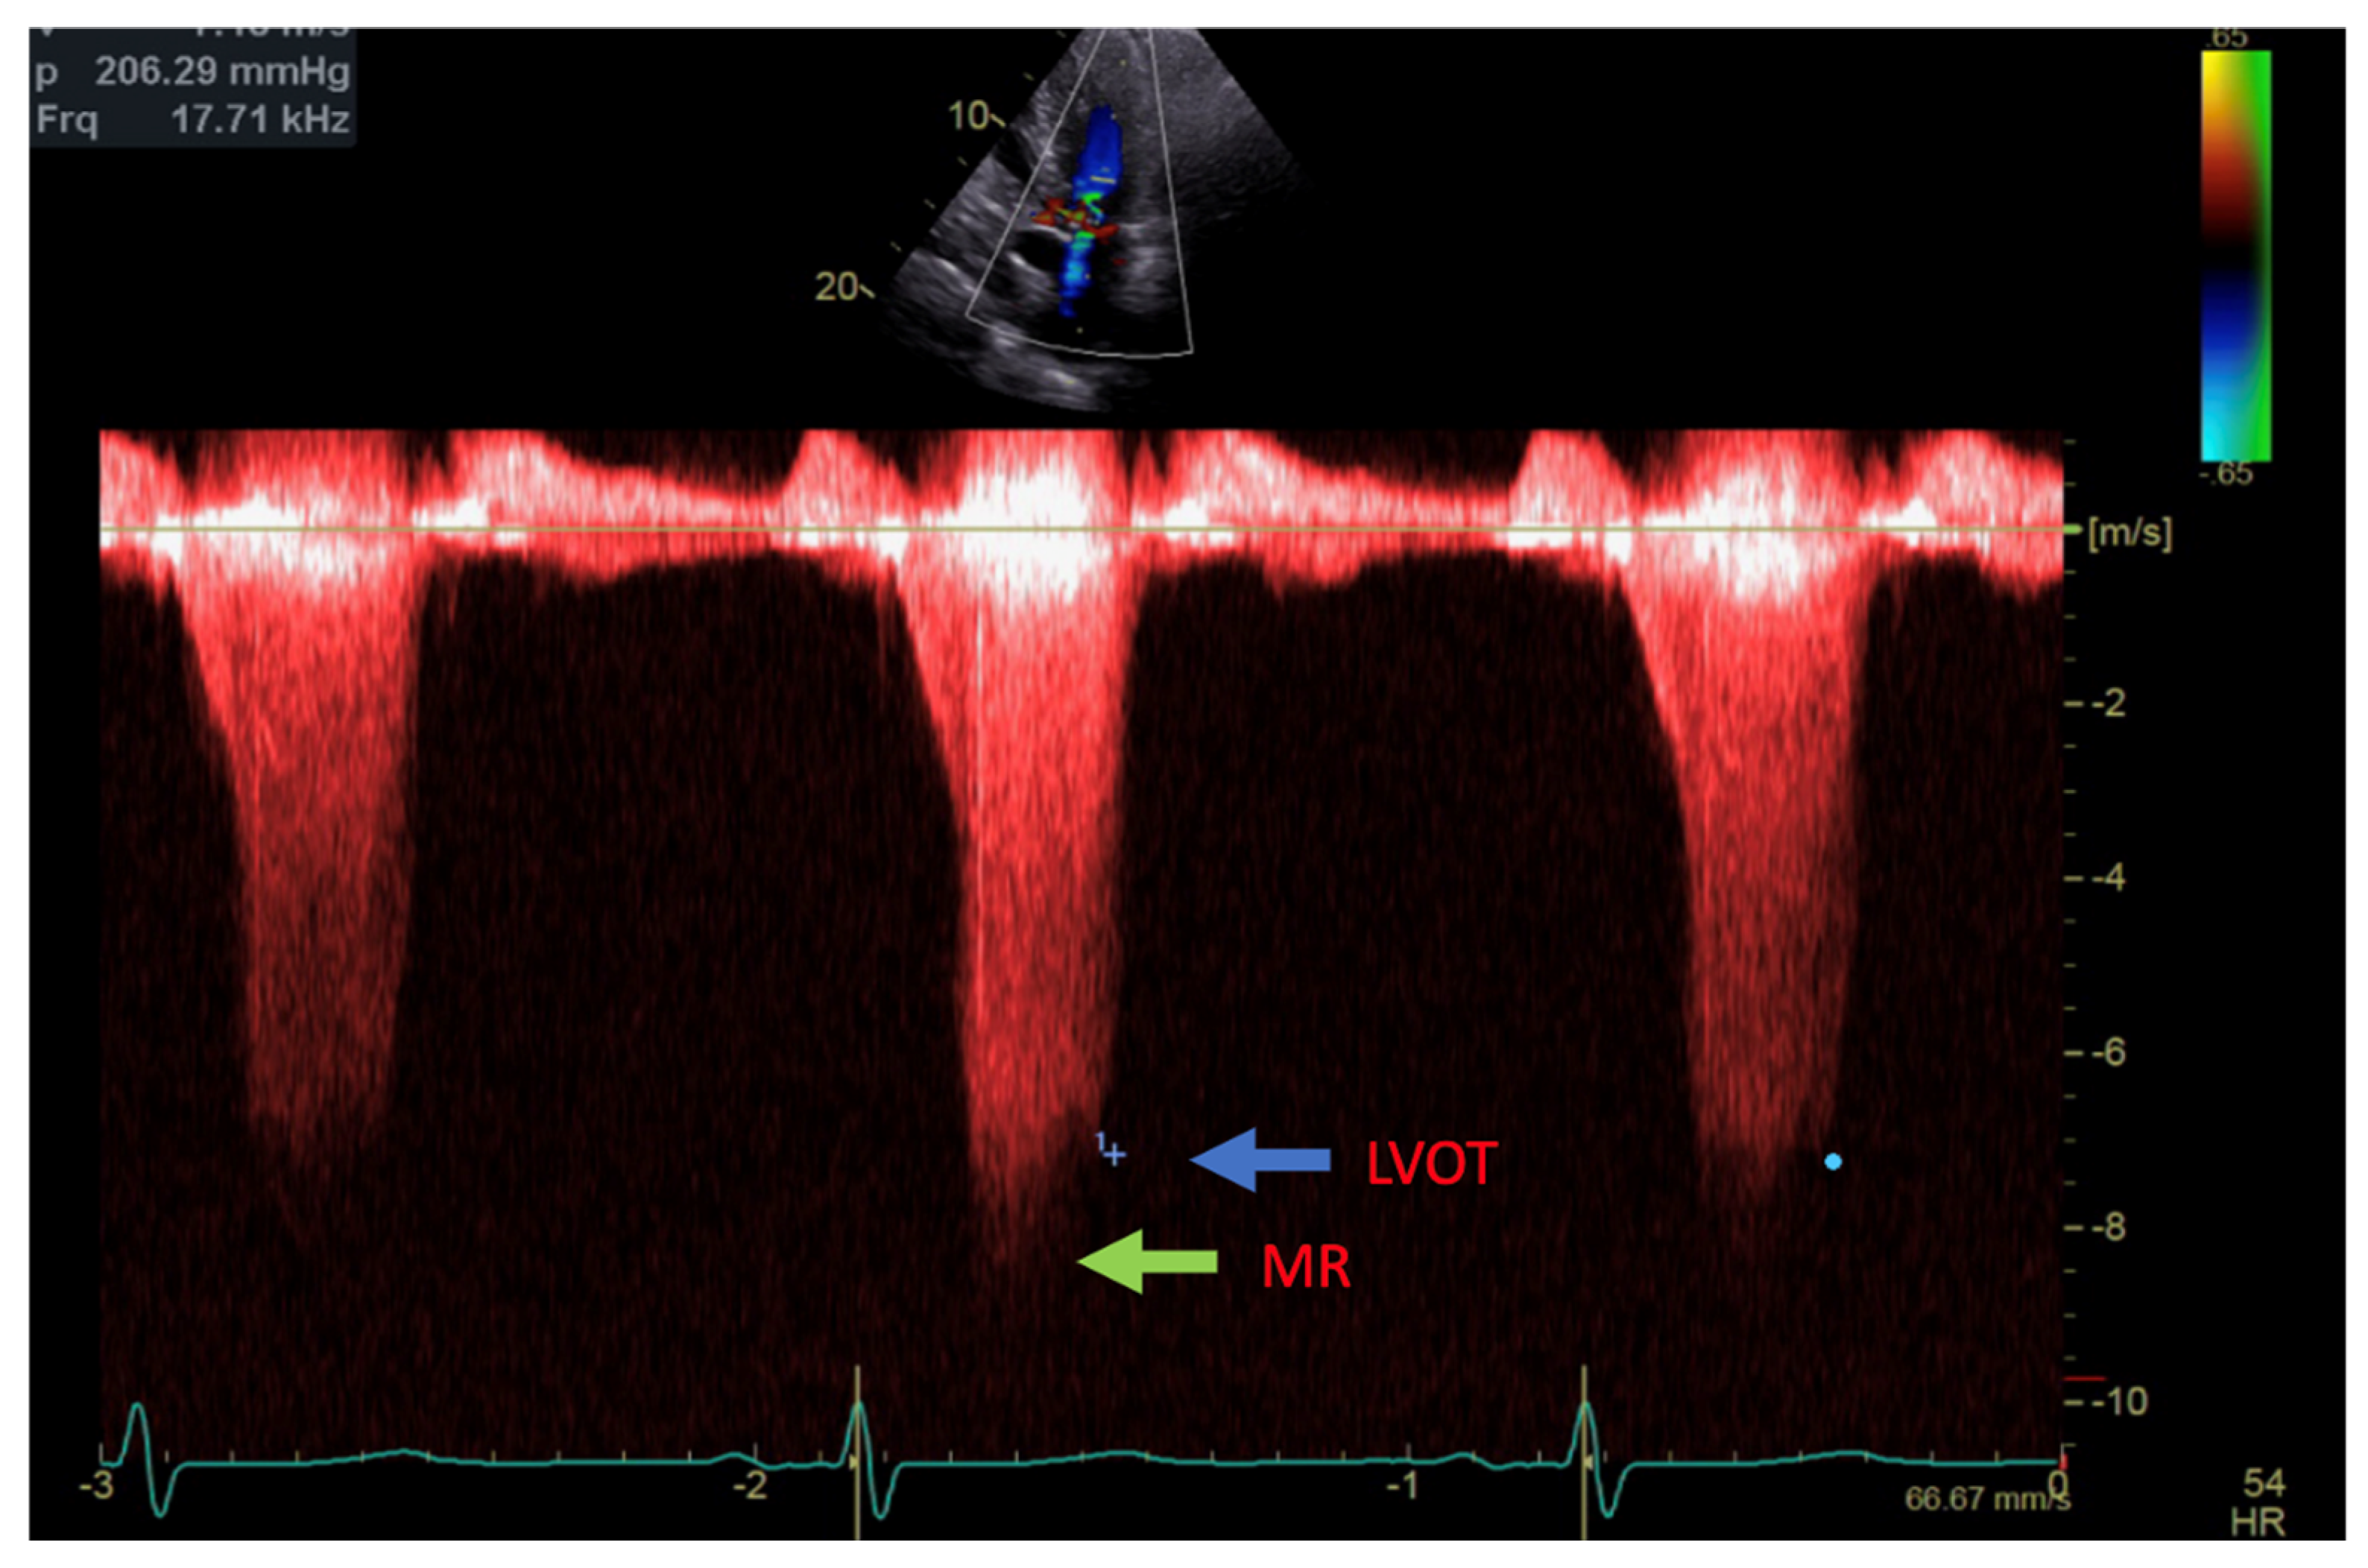

Figure 2.

Continuous Doppler with two jets showing MR (green arrow) and LVOT gradient (blue arrow).

Transthoracic echocardiogram (TTE) showed severe asymmetric left ventricular hypertrophy, preserved left ventricular ejection fraction at 65–70%, systolic anterior motion (SAM) of the mitral valve (Figure 1 and Supplementary Video S1), left ventricular outflow tract (LVOT) obstruction with a peak velocity of 7.1 m/s at rest and an eccentric, posteriorly directed mitral regurgitant jet (Figure 2). Pharmacological myocardial perfusion SPECT with gated imaging was obtained one year prior to presentation and showed normal myocardial perfusion, left ventricular volume and systolic function. Cardiac magnetic resonance imaging showed left ventricular hypertrophy with a maximal thickness of 1.7 cm at the mid-ventricular septum and late gadolinium enhancement in the lateral and inferior half of the left ventricle, the basal inferolateral wall, the apical lateral walls and the apical anterior wall (Figure 3a,b). These findings were consistent with a diagnosis of HCM with outflow tract obstruction; thus, the patient was started on beta blockers.